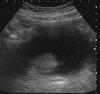

Μalakoplakia is a rare inflammatory condition of the urogenital tract. The most frequently affected organ is urinary bladder. This condition has features of a granulomatous inflammation, the pathogenesis of which is not well understood. In this study, we presented a case of urinary bladder malakoplakia associated with advanced obstructive uropathy and renal failure.